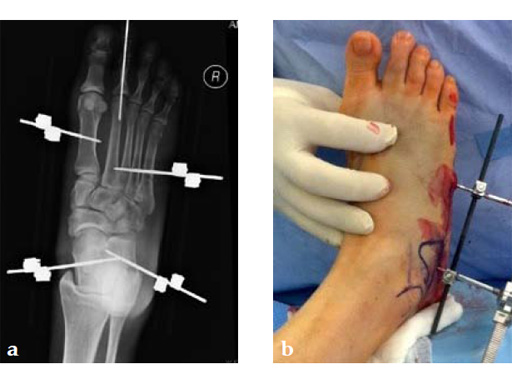

The patient was treated with arthrodesis of the talonavicular and subtalar joints. The compression/ distraction device was used to restore the length of the medial column. The articular surface of the subtalar joint was prepared arthroscopically. The talonavicular joint was debrided then packed with a tricalcium matrix. Length was maintained using a locking X-plate. The subtalar joint was then fixed with a 6.5 mm headless compression screw.